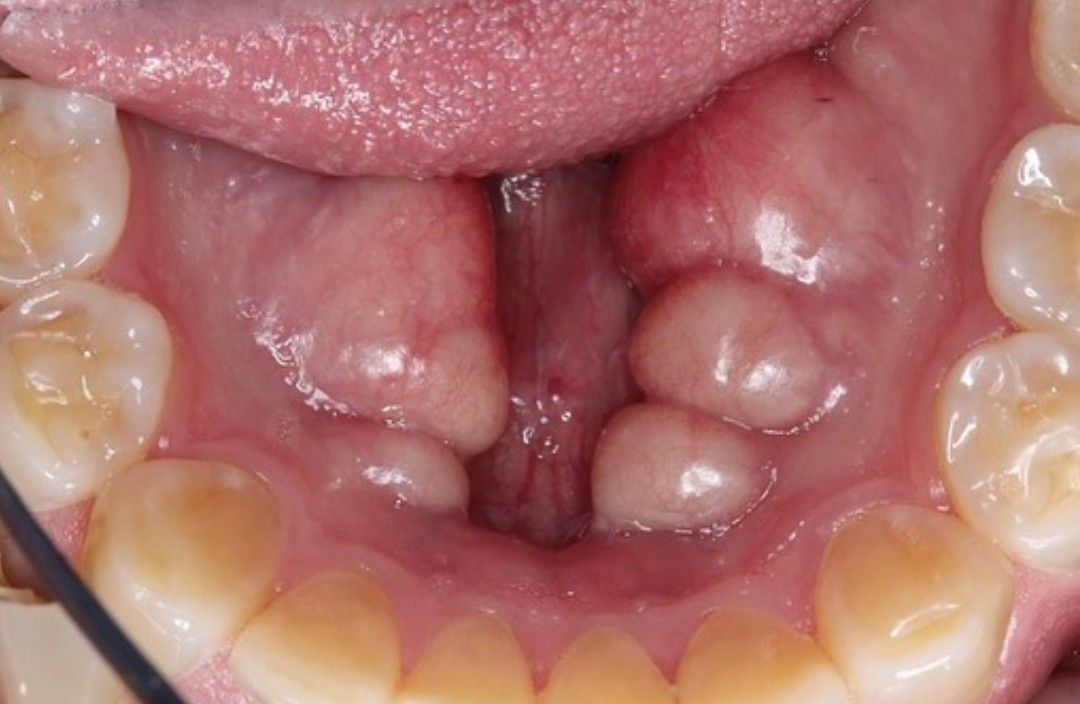

Mandibular Tori -PreOp

Yeah the picture of Mandibular Tori Preoperative.